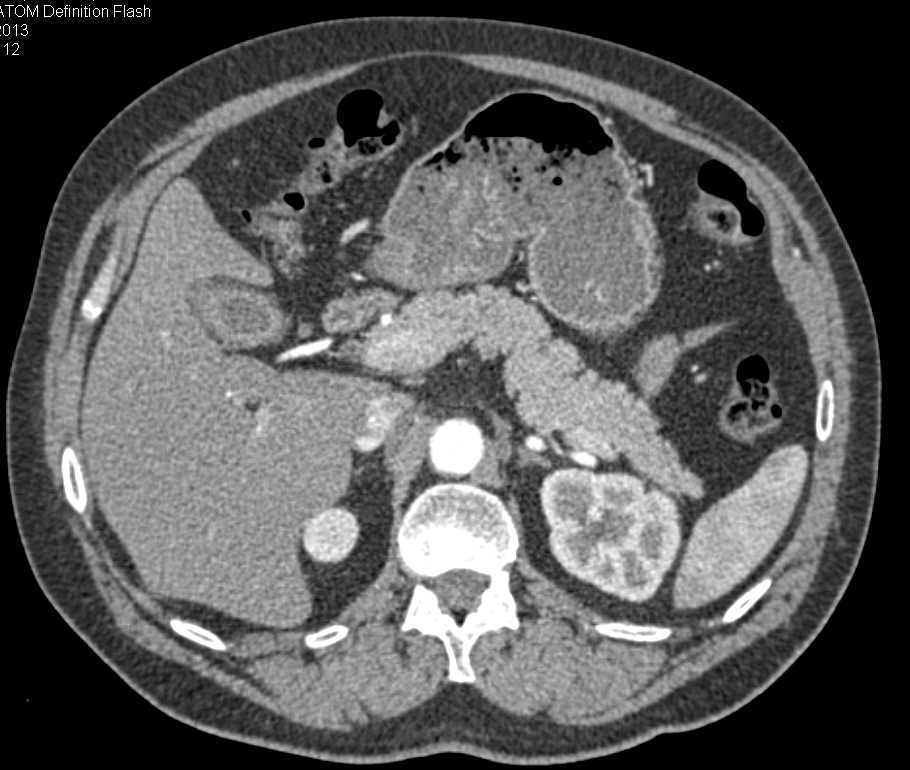

Transitional Cell Cancer (TCC) of the Distal Left Ureter